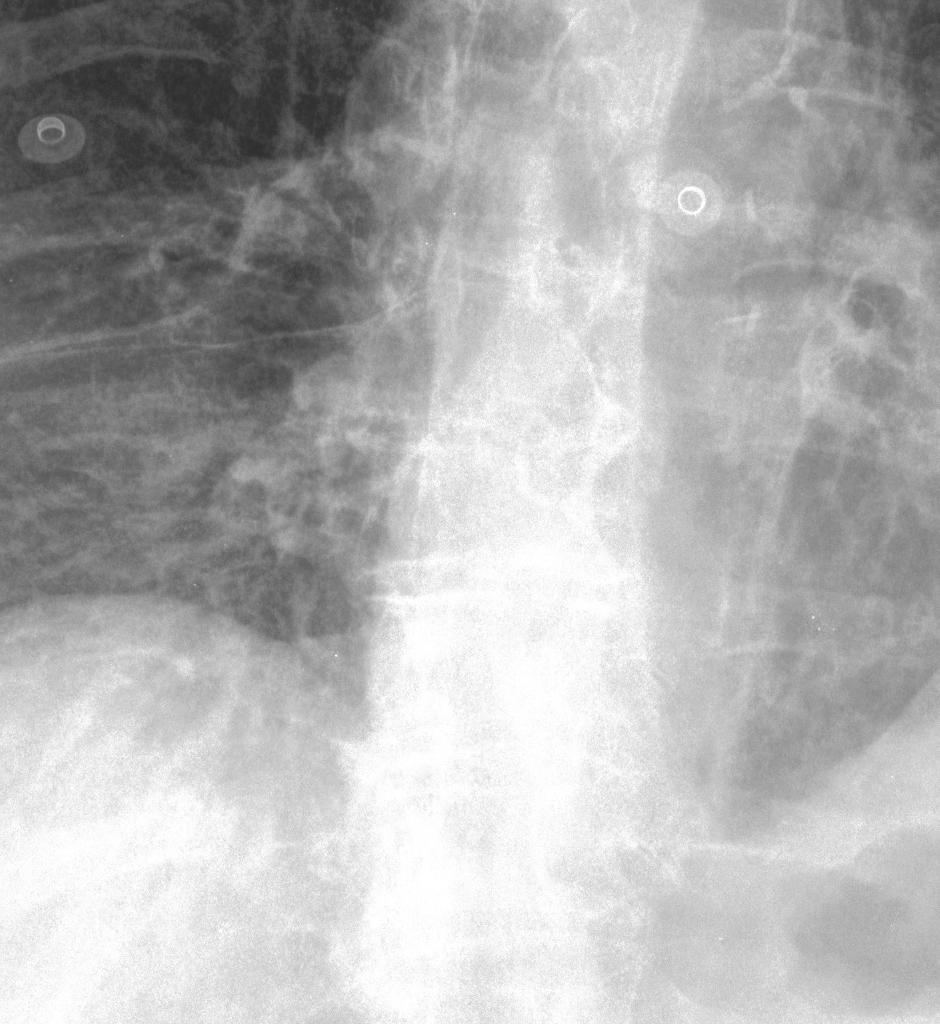

Statistical analysis using the Wilcoxon rank test (applied to scores within the range of mean ±\pm 1.96 standard deviations) confirms the significance of improvements in TC, LPC-SI, TMQI, and PIQE (p<0.05p<0.05). Interestingly, the model without GL exhibits significantly higher entropy (p<0.05p<0.05), although this metric alone does not necessarily indicate superior structural or perceptual quality. Furthermore, gradient map visualizations (see Fig. 5) provide additional insight into the GL’s contribution, revealing clearer object outlines and finer details in comparison to settings without the GL.

Figure 5: Visualization of gradient maps: (a) Original image fragment, (b) gradient of the original fragment, (c) gradient with single HFC as guidance, (d) gradient without GL, and (e) gradient with GL